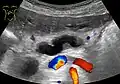

Ultrasonography of a dilated pancreatic duct (in this case 9mm) due to pancreatic cancer.